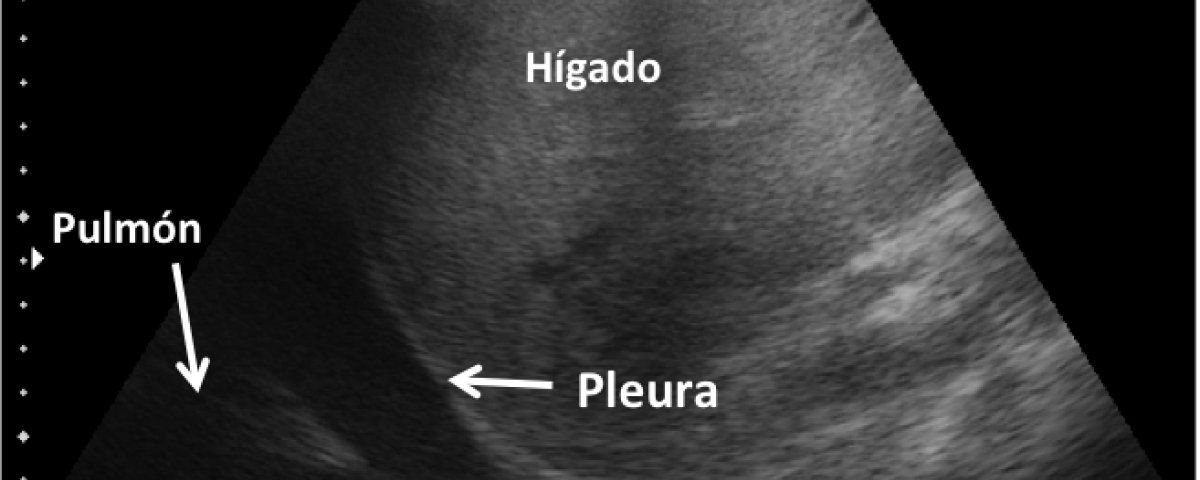

- ECOGRAFIA PLEURAL Y PULMONAR